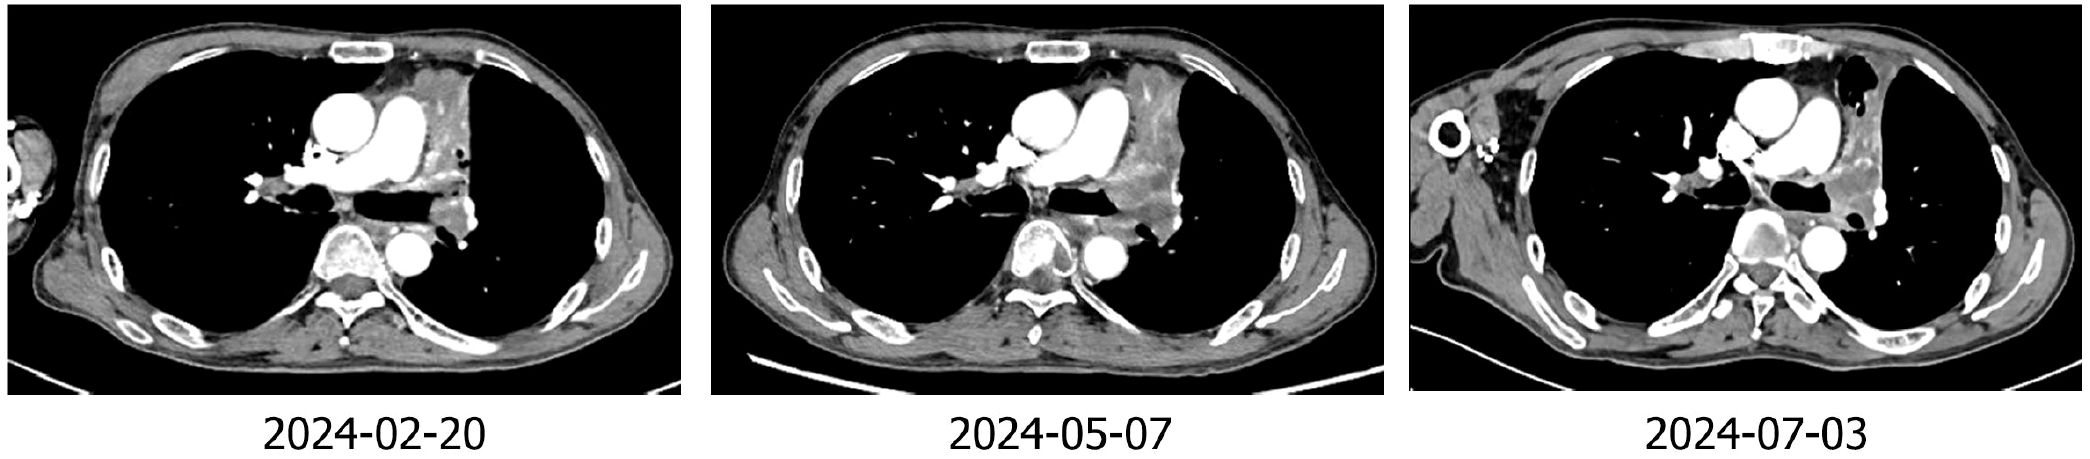

The patient was Li XX, 58 years old, male, smoking index 500. In 2022-02, the patient was treated for “cough”. Chest CT revealed a soft tissue shadow in the left hilum of the lung, multiple enlarged lymph nodes in the mediastinum and hilum of the lung, and nodules in the outer basal segment of the lower lobe of the right lung. Fibrobronchoscopy revealed a new protuberant lesion that was located in the opening of the upper left lobe, blocking the lumen. Forceps biopsy was performed. Pathological analysis of the specimen revealed large-cell neuroendocrine carcinoma of the upper left lobe. The immunohistochemical results were as follows: Syn (+), CD56 + (weak), CgA (-), CK (focal point +), CK5/6 (-), Ki -67 (+ 80%), NapsinA (-), P40 (-), and vera.ttf (+) - 1 (Figure 1). The patient was diagnosed with left lung large-cell neuroendocrine carcinoma, stage cT1N2M1aIVA (right lung). From 2022-2-18 to 2022-7-17, he received chemotherapy consisting of the EP regimen (etoposide 0.-4+ carboplatin 400 mg/d1) for 6 cycles, and the best efficacy evaluation was a PR. A review of a chest CT image taken on 2022-08-11 revealed a space-occupying lesion of the left upper hilum, which measured approximately 4.3*3.6 cm in size and was significantly larger than before. Multiple enlarged lymph nodes were observed in the mediastinum and hilum. The revised diagnosis after a complete examination was as follows: stage cT4N3M1aIVA left lung large-cell neuroendocrine carcinoma (right lung). In 2022-09, the patient was enrolled in the “randomized, open, multicentre phase III clinical study to evaluate the efficacy and safety of sofratinib combined with toripalimab versus FOLFIRI as second-line treatment for advanced neuroendocrine carcinoma”, and he was randomized to receive chemotherapy alone. Chemotherapy with the FOLFIRI regimen was performed for 4 cycles: 2022-09-09, 2022-09-24, 2022-10-09 and 2022-10-25. During chemotherapy, the patient’s gastrointestinal reaction was grade III, with no obvious bone marrow suppression. PD was evaluated after 4 cycles (target lesion: left pulmonary lesion 7.5 cm→9.3 cm), and consequently, a clinical trial was conducted. The patient was treated with sofratinib combined with toripalimab in 2022-11-18, 2022-12-30, and 2023-01-16. After 3 cycles of treatment, the mass in the upper lobe of the left lung was smaller than before (9.3 cm→7.9 cm), and the efficacy was evaluated as SD (15%↓). During the treatment period, the patient experienced no adverse events such as rash, bleeding, thrombosis, diarrhoea, abdominal pain, or constipation. Furthermore, the patient’s cough and wheezing were significantly relieved. Sofratinib combined with toripalimab was administered to the patient on 2023-02-10, 2023-03-10, 2023-04-03, and 2023-5-10 because of “aggravation of cough and sputum”, and a reexamination of the chest with enhanced CT at our hospital revealed a mass in the left upper lobe of the lung complicated with obstructive inflammation and an increased range of obstructive atelectasis (9.1 cm). Considering “lung infection”, targeted therapy was suspended. After anti-infective treatment, the patient’s cough and sputum symptoms were alleviated. A review of the patient’s chest enhanced CT imaging on 2023-5-22 revealed a mass in the upper lobe of the left lung, the overall area of which was reduced (7.9 cm), indicating effective anti-infection. On 2023-06-07, 2023-06-21, 2023-07-06, 2023-07-25, and 2023-08-14, treatment with sofratinib combined with toripalimab was continued. In 2023-08-15, CT reexamination revealed a mass in the upper lobe of the left lung with obstructive inflammation and atelectasis, the area of which was smaller than before. The efficacy was evaluated as a PR (31%↓). Treatment with sofratinib combined with toripalimab was continued, and the efficacy evaluation continued to show a PR in 2023-10-25 and 2023-12-12 (Figure 2). At the beginning of 2024.2, the patient felt that his cough was aggravated, and chest and abdominal CT findings were reviewed on 2024.2.20 and compared with those on 2023-12-12. CT revealed the following: 1. The mass in the upper lobe of the left lung indicated lung cancer with obstructive inflammation and obstructive atelectasis, and the overall area was larger than before (9.1×3.3 cm). 2. Compared with those in the anterior segment, the ground glass nodules in the upper segment of the right lung were newly increased, and the ground glass nodules in the posterior and anterior segments of the lower right lung were not clearly displayed this time. 3. Multiple lymph nodes in the mediastinum and both pulmonary portals showed enlargement. To indicate disease progression, the tumour was evaluated as PD (60.6%↑) (Figure 2). On 2024-2-22, bronchoscopy revealed a left upper lobe tumour with bleeding. Pathological results of a puncture biopsy of the left upper lobe of the lung revealed large necrosis and a small number of focal atypical cells; these findings combined with those from the clinical and immunohistochemical analyses were consistent with poorly differentiated carcinoma and high-grade neuroendocrine carcinoma, NOS. Immunohistochemical results revealed CKpan weak (+), CAM5.2 weak (+), vera.ttf (+) - 1, p40 (-), SYN (+), CGA (-), CD56 (-), P53 (+ 70%), RB1 (+), Ki - 67 (hot zone + 75%). The patient was treated with the combined EP regimen (etoposide 130 mg D1-3+ cisplatin 30 mg D1-3) on 2024-02-29 and 2024-03-22. After 2 cycles of chemotherapy, the therapeutic effect was evaluated as PD (new bone metastasis). On 2024-05-10, 2024-06-02, and 2024-06-25, the treatment regimen was replaced with everolimus combined with toripalimab for 3 cycles, while desumab was given to inhibit bone destruction. The review efficacy evaluation performed on 2024-07-03 revealed SD (21.4% ↓) (Figure 3); currently, the patient is continuing this new targeted immunotherapy regimen.

Figure 3. Imaging of the patient during treatment with the toripalimab-plus-EP regimen and the everolimus-plus-toripali regimen.